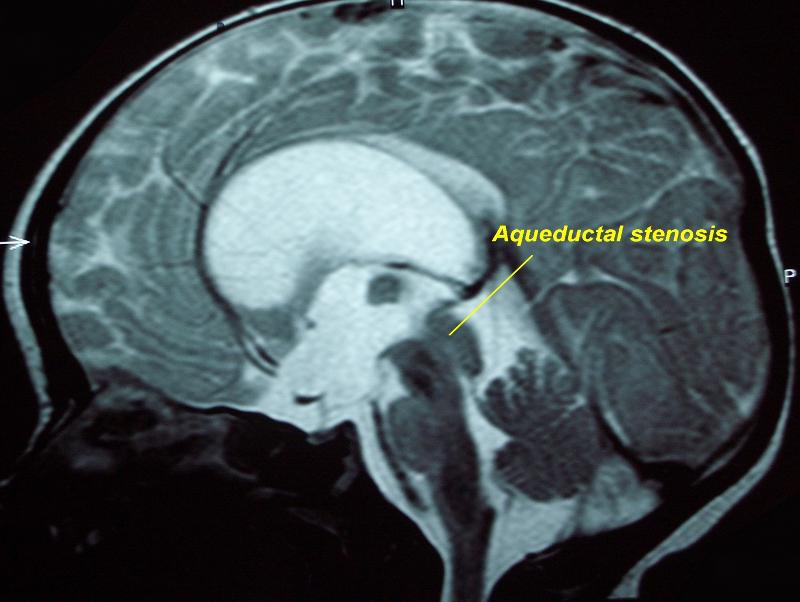

what is this aqueductal stenosis causing

hydrocephalus on MRI

what space would be more dilated: space after aqueductal stenosis or before it

before